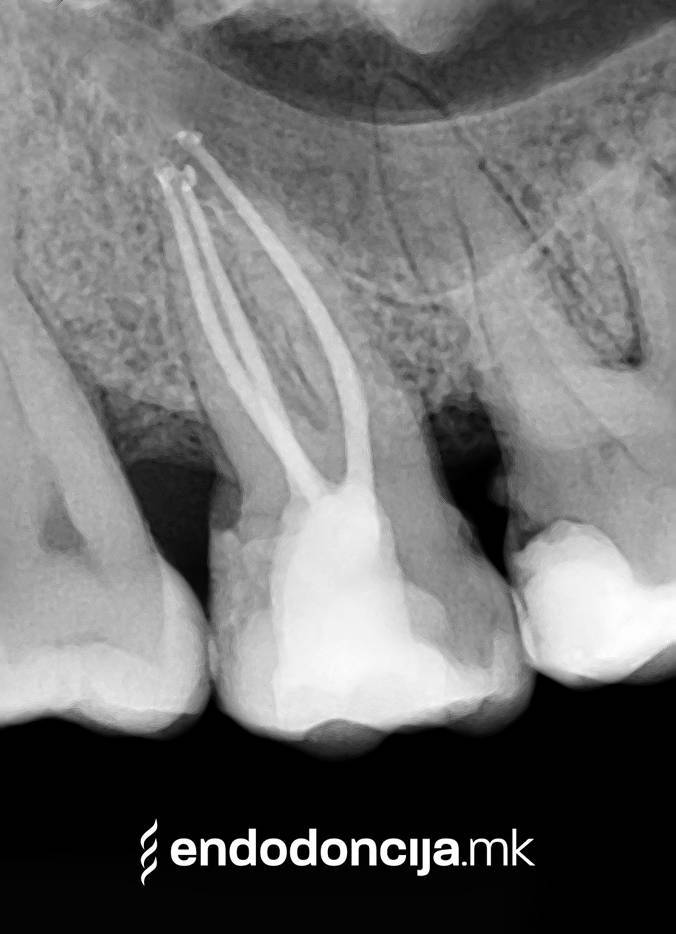

Σε περίπτωση ανανέωσης της θεραπείας του ριζικού καναλιού (αναθεώρηση) παλιά γεμίσματα ρίζας που δεν ήταν επιτυχημένα και ως εκ τούτου ήταν η αιτία φλεγμονών και πόνου, μπορούν να αφαιρεθούν και να ανανεωθούν εξειδικευμένα. Αυτή η θεραπεία εξαλείφει τις φλεγμονές στην περιοχή της ρίζας και καθίσταται δυνατή η πλήρης ανάρρωση.

Εκτός από την ανίχνευση των ριζικών καναλιών, η ενδελεχής προετοιμασία και η απολύμανση του ριζικού σωλήνα είναι η προϋπόθεση για μια επιτυχημένη συνολική θεραπεία. Μέσω της χρήσης των νεότερων οργάνων και αντιβακτηριακών διαλυμάτων, όλα τα υπολείμματα ιστών και τα βακτήρια που υπάρχουν μπορούν να εξαλειφθούν.

Κατά τη διάρκεια της επεξεργασίας του ριζικού σωλήνα, τα λεπτά όργανα ενδέχεται να σπάσουν. Αυτό μπορεί να αποτελέσει εμπόδιο για την πλήρη προετοιμασία και τον καθαρισμό του ριζικού σωλήνα. Με μια μικροσκοπική επεξεργασία του ριζικού σωλήνα μπορεί να είναι δυνατή η απομάκρυνσή τους υπό ορισμένες συνθήκες, χωρίς να καταστρέφεται η ουσία των δοντιών.